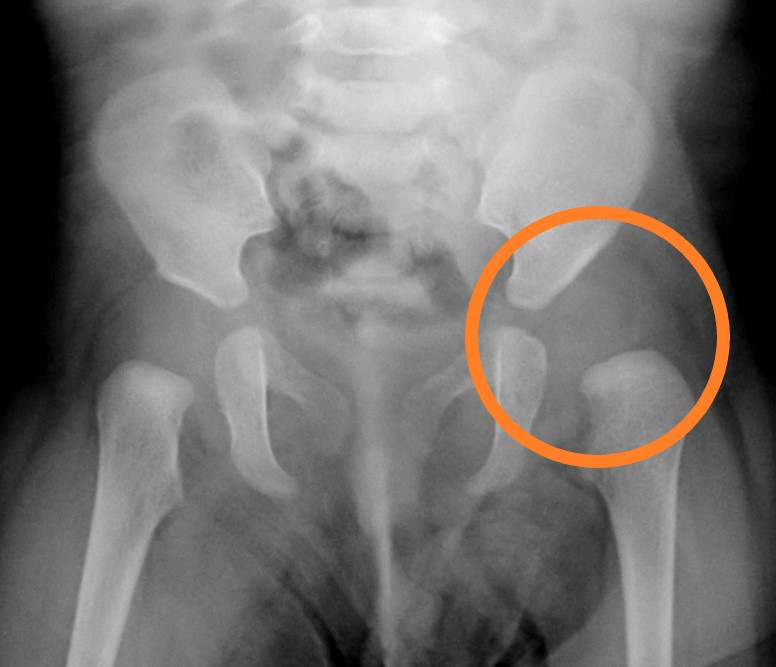

10. 股関節脱臼の診断方法(検査法)

診断にはエコー(超音波検査)が極めて有用です。これまで日本では開排制限(お股の開きが硬いこと)とレントゲン(X線)検査での診断が行われてきました。完全に脱臼している場合には、骨の大きなズレのため診断が可能です。しかし今にもはずれようとしている亜脱臼のような微妙な状態は、レントゲン(X線)ではどうしてもわかりにくいのが事実です。その理由は開排制限のない関節の柔らかい脱臼が存在すること、そして股関節の大半が軟骨でできていてレントゲンには写らないことがあげられます。レントゲン検査を受けたにもかかわらず、あとから脱臼がわかったような場合、そうした微妙な状態であったと考えられます

| エコー(超音波)では軟骨もしっかり見えるため、この微妙な状態までわかるような検査システムになっています。世界的な標準方法がグラフ(Graf)法です。海外の股関節脱臼のための健診先進国では、必ずエコー(超音波)で検査することになっています |

お母さんなど家族に股関節脱臼の家族歴がある場合、自分と同じような苦労をさせていたくないと、大変心配になり、早く脱臼がないだろうか心配になります。また股関節の開きが硬いので、受診したのに異常なしと言われても心配な場合もあります。そうした心配が払拭されない場合には、ぜひエコー検査のできる病院の受診をお勧めします。各都道府県で専門病院は必ずありますので、電話でお問い合わせの上受診ください

股関節脱臼が無事整復されたのちは、股関節の成長を定期的なX線検査などで見守りますが、股関節のかぶりが浅い「寛骨臼形成不全(臼蓋形成不全)」という後遺症がひどい場合、骨盤補正手術(骨盤骨切り術)を行います。できれば就学前に大きな治療を終わらせておく治療方針となります